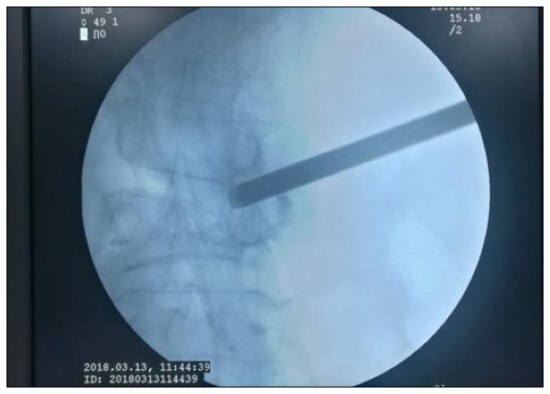

经充分术前准备后,于2018年3月13号下午,由袁中山主任和他的团队实施微创椎间孔镜手术治疗,手术在局麻下顺利完成,历时2小时左右,手术切口8mm,手术出血仅约10ml,术后病人腰腿痛明显好转,翻身不痛了,咳嗽也敢咳了,也能下床走路了,患者又露出开心的笑容。术后患者高兴的说:“感谢你们用这样一种神奇的方法解除了我的病痛,你们本身真大!”。患者已于2018年3月28日顺利出院。